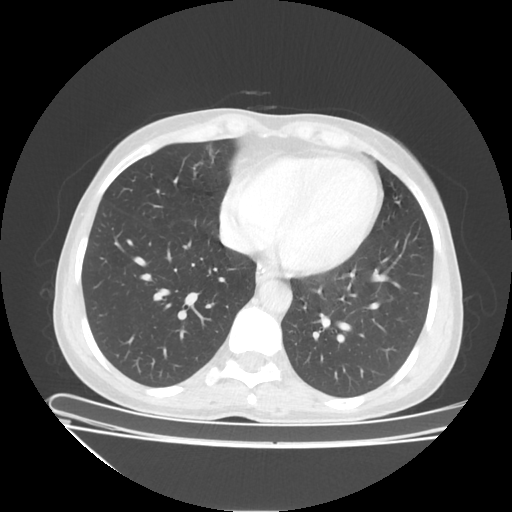

Reconstructed NATIVE CT scan (cycle consistency)

Full window (WL 1023.5, WW 4095 β†’ Low βˆ’1024, High +3071)

Lung window (WL -600, WW 1500 β†’ Low βˆ’1350, High +150)

Mediastinum window (WL 40, WW 400 β†’ Low βˆ’160, High +240)